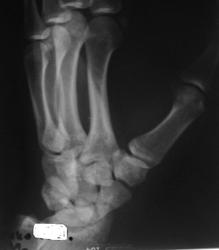

Случай №2 Молодой спортсмен, около 6 месяцев назад упал на руку. Лечился. Ставили перелом ладьи.Вопрос только в том: "А сросся ли он?". Нет ли тут асептического некроза?

Консолидация четко прослеживается. Пациента что-то беспокоит?

А во втором... Консолидация есть однозначно. Об этом говорит хотя бы одно то, что за полгода при занятиях спортом не произошло вторичного смещения отломков (или полгода была иммобилизация?). Асептического некроза не нахожу.

Боль беспокоит в проекции ладьи или более разлиты по площади? Может, стоит думать о сопутствующий повреждениях суставных образований (менисков, связок, сухожилий)?

Во 2 случае - оба снимка надо бы выполнять, когда предплечье параллельно кассете в т.ч. А так фасетка луча становится эллипсом и позиционируется на ладью, особенно в косой проекции. Кистовидная перестройка в зоне консолидации перелома тела ладьи без ее деформации. Боль при отсутствии явной костной патологии может исходить из окружающих мягкотканных структур, разнообразием которых наградил Бог человеческую кисть, дабы тот мог в поте лица зарабатывать себе на хлеб насущный не только тяжелым ратным трудом, но и творческими профессиями, требующими тонкой моторики рук.